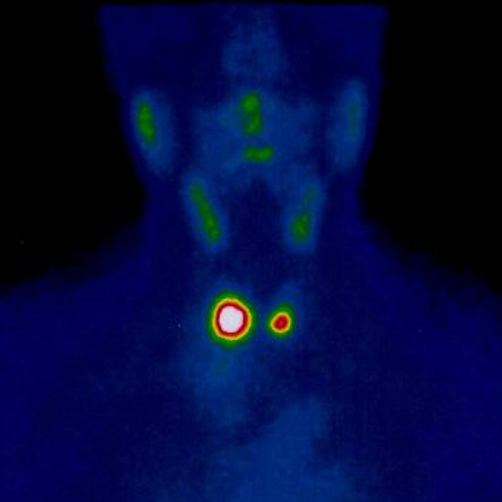

La exploración consiste, previa preparación del paciente, en la inyección intravenosa de un radiofármaco y la obtención de imágenes a las 4 y 24 horas postinyección.

Tipo de gammagrafía con radionúclido que se usa para encontrar tumores carcinoides y de otro tipo. La octreotida radiactiva, un medicamento similar a la somatostatina, se inyecta en una vena y se desplaza por el torrente sanguíneo.